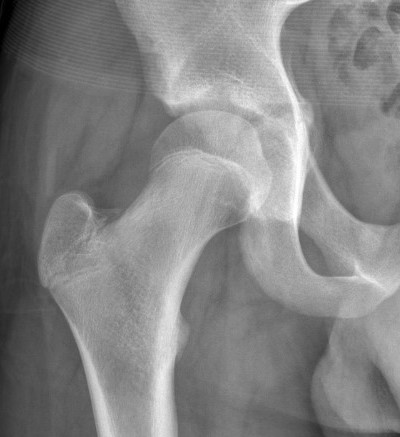

Acetabular Fractures

Triradiate fractures

- uncommon

- usually from extension of adjacent rami and iliac fracture

- usually stable

Complication

- child < 10

- early closure triradiate cartilage

- acetabular dysplasia

Management

Tri-radiate fracture

- skeletal traction

- CT

- if severely displaced fragment ORIF with smooth pins

Physeal bar across triradiate cartilage

- follow up all displaced & non displaced

- consider bony bidge excision and fat graft